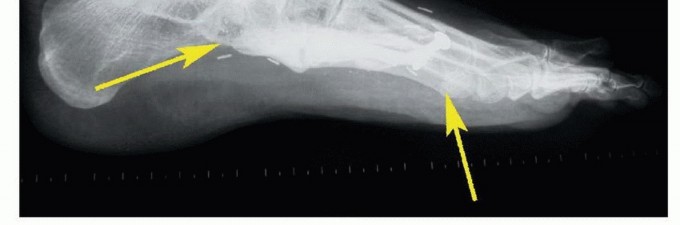

- الأشعة السينية (X-rays): هي الخطوة الأولى لتحديد ما إذا كان الورم عظميًا، وتقييم حجمه، وشكله، ومدى تأثيره على بنية العظم.

- التصوير بالرنين المغناطيسي (MRI): يوفر صورًا مفصلة للغاية للأنسجة الرخوة (العضلات، الأوتار، الأعصاب، الأوعية الدموية) والعظام، مما يساعد على تحديد مدى انتشار الورم بدقة، وعلاقته بالهياكل المحيطة. يعتبر التصوير بالرنين المغناطيسي ضروريًا لتخطيط الجراحة.

- التصوير المقطعي المحوسب (CT Scan): يستخدم لتقييم تفاصيل بنية العظام، خاصة في حالات الأورام العظمية، ويمكن استخدامه لتقييم انتشار الورم إلى الرئتين (في حالات الأورام الخبيثة).